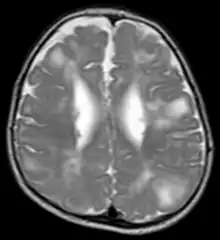

Classic intracranial manifestations of TSC include subependymal nodules and cortical/subcortical tubers.[6]

The tubers are typically triangular in configuration, with the apex pointed towards the ventricles, and are thought to represent foci of abnormal neuronal migration. The T2 signal abnormalities may subside in adulthood, but will still be visible on histopathological analysis. On magnetic resonance imaging (MRI), TSC patients can exhibit other signs consistent with abnormal neuron migration such as radial white matter tracts hyperintense on T2WI and heterotopic grey matter.

Subependymal nodules are composed of abnormal, swollen glial cells and bizarre multinucleated cells which are indeterminate for glial or neuronal origin. Interposed neural tissue is not present. These nodules have a tendency to calcify as the patient ages. A nodule that markedly enhances and enlarges over time should be considered suspicious for transformation into a subependymal giant cell astrocytoma, which typically develops in the region of the foramen of Monro, in which case it is at risk of developing an obstructive hydrocephalus.

A variable degree of ventricular enlargement is seen, either obstructive (e.g. by a subependymal nodule in the region of the foramen of Monro) or idiopathic in nature.